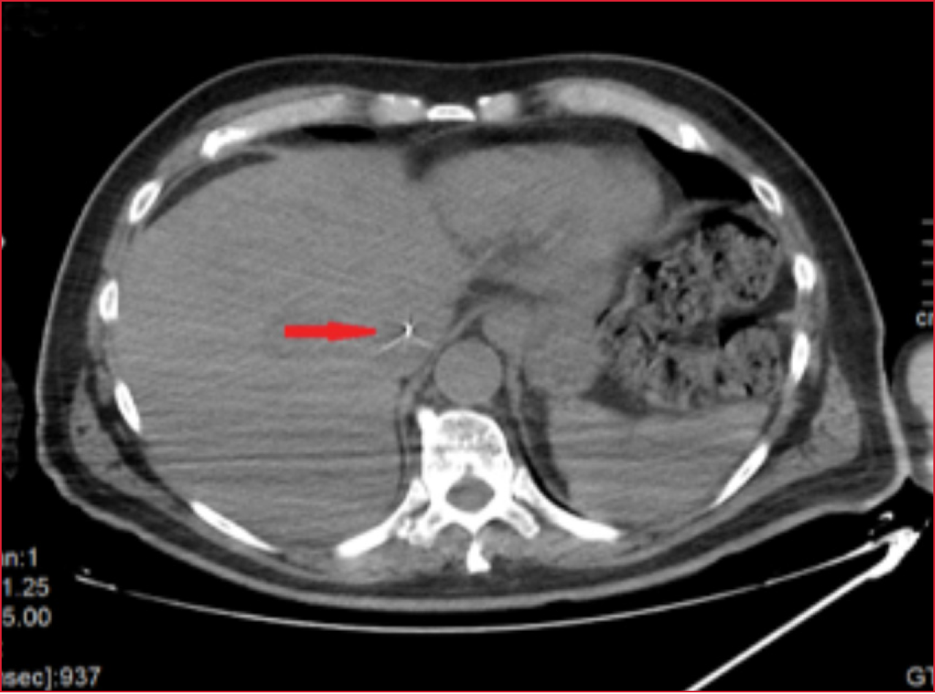

Se completó el

estudio con una tomografía computarizada, que mostró la progresión de la guía

hasta la vena cava inferior tanto en el corte coronal (Figura 2) como en el

corte axial (Figura 3).

Figura 3. Tomografía computarizada (corte axial). Se visualiza la guía metálica en la vena cava inferior (flecha roja).